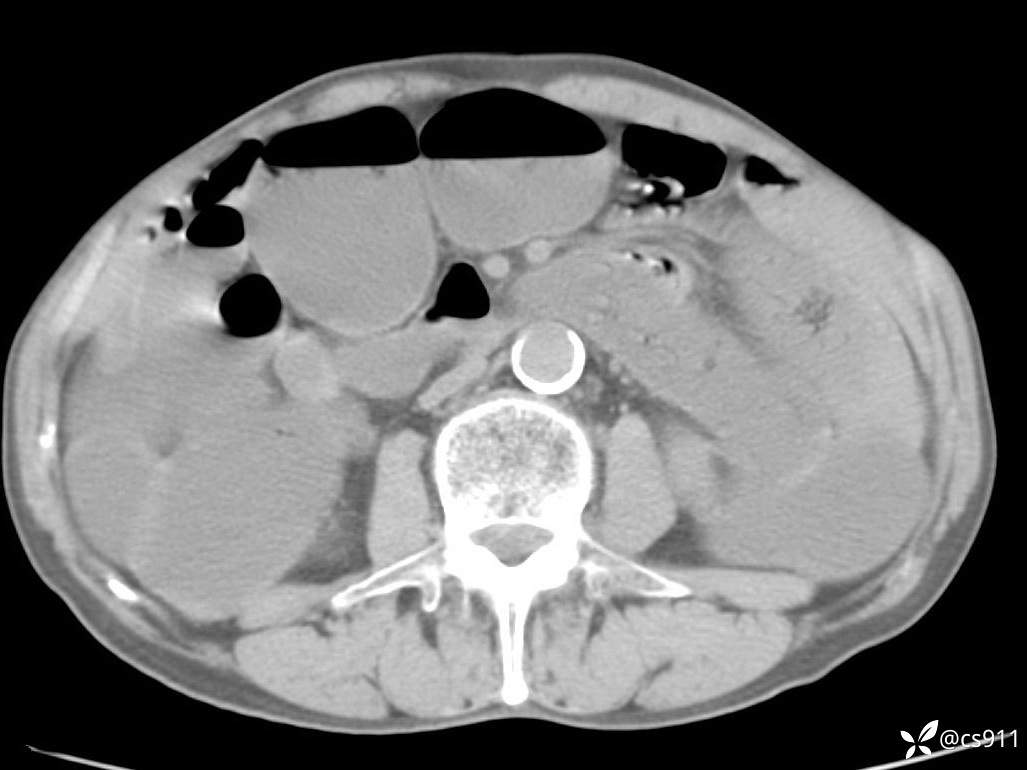

急腹症之急诊CT,原因?答案公布

男,77岁,腹痛、腹胀伴恶心呕吐1天。呕吐胃内容物,非喷射性呕吐,有咖啡色样胃内容物,诉有胃穿孔病史。查体:全腹平,下腹部压痛,全腹无反跳痛,叩诊呈浊音,移动性浊音阴性,肠鸣音减弱,1-2次/分。肛检:直肠未扪及明显肿物,可触及大量粪块。

T 36.6℃ P 80次/分 R 26次/分 BP 100/60mmHg

白细胞(WBC) H 14.55 10e9/L 4-10

中性粒细胞百分率(NEUT%) H 85.7 % 40-75

血淀粉酶(AMY) HH 1859 U/L 35-135

癌胚抗原(CEA) H 27.44 ng/ml 0-5

呕吐物 潜血试验 * 阳性 阴性

患者轮椅入室检查神志清楚, 能配合摆位和呼吸